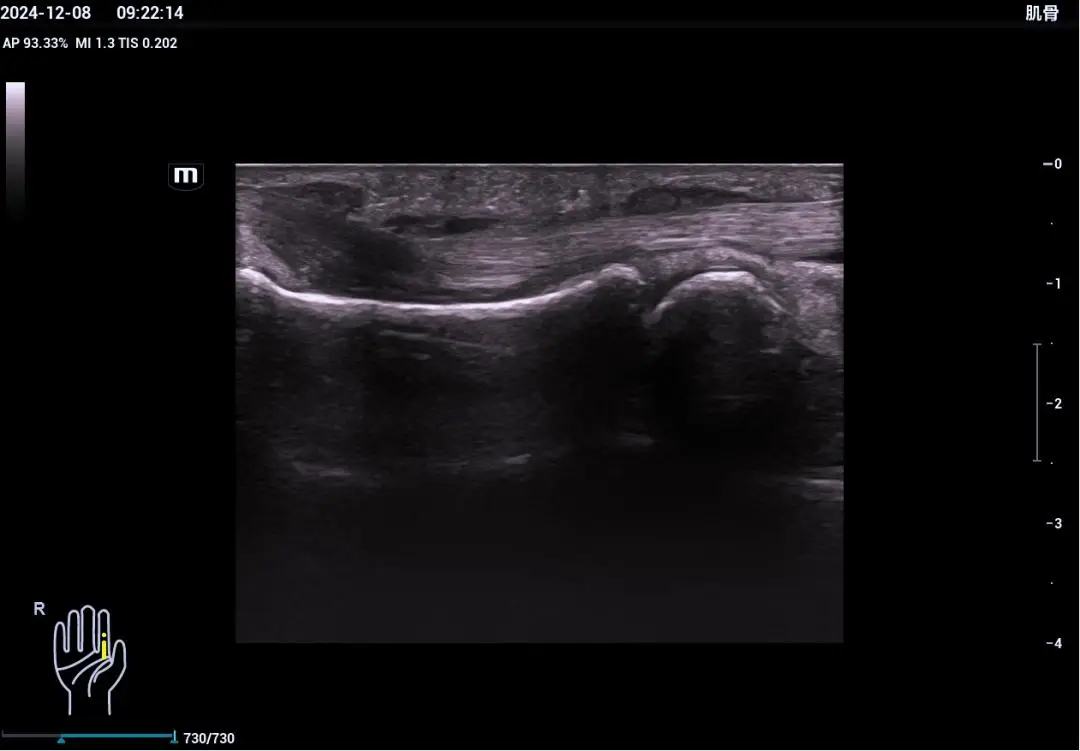

肌骨超声是近几年发展起来的一项新兴技术,它利用超声技术对肌肉、骨骼、神经、肌腱、韧带等组织进行疾病的诊断,并可用于超声引导下的治疗。这一技术的发展得益于超声硬件和软件技术···...